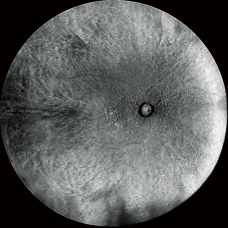

Retro后照模式

彩照和Retro后照模式圖像(Drusen)

Retro后照模式是一種富有特色的無創檢查技術,用于檢測脈絡膜的病理改變。

這種成像方式通過采集玻璃膜疣、水腫及其他細微的脈絡膜視網膜病變引起脈絡膜中散射的紅外光來立體的呈現病灶。